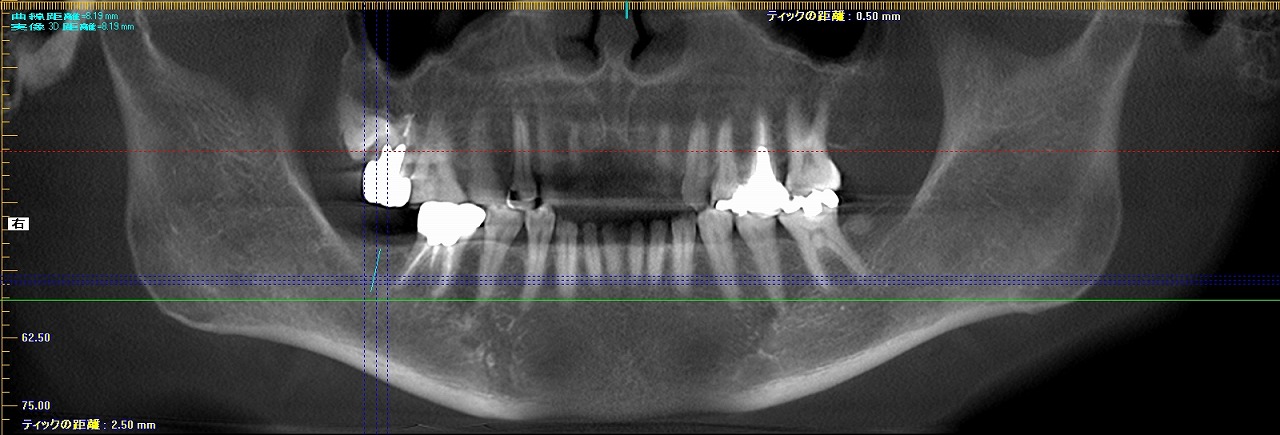

右下7番インプラント部の上部構造 セラミックにて治療|お知らせ |広島市安佐南区の歯科医院 右下7番インプラント部の上部構造 セラミックにて治療 トップ お知らせ・ブログ お知らせ 右下7番インプラント部の上部構造 セラミックにて治療 右下7番インプラント部の上部構造 セラミックにて治療 2か月半待って印象後、アバットメントとセラミックの上部構造を 作成していきます 埋入前のパントモになります 埋入後のパントモになります 距離がかなり厳しいところになります 埋入して3か月には歯が入るべく上位部構造が出来上がりました チタンにてアバットメントと呼ばれる土台は作成していきます 口腔内にて きれいに入り機能していきます インプラント埋入は厳しい場所柄になりますが 無事に歯が入りました Web診療予約 初めての方へ 選ばれ続ける理由 院内設備について 歯が痛いしみる一般歯科 歯がぐらぐらする歯周病 健康な歯を保ちたい予防歯科 子供の虫歯予防をしたい小児歯科 銀歯をセラミックに審美歯科 白い歯を目指しませんか?ホワイトニング 矯正専門医がいるので安心矯正歯科 抜けた歯を補いたいインプラント・入れ歯 医院案内 スタッフ紹介 メリィハウス歯科クリニックオフィシャルホームページ ラベンダー歯科クリニックオフィシャルホームページ お知らせ・ブログ ホーム 診療科目 一般歯科 歯周病治療 予防治療 小児歯科 審美治療 ホワイトニング 矯正歯科 入れ歯・インプラント マウスピース矯正 初めての方へ 院長・スタッフ 設備紹介 医院案内・アクセス メニューを閉じる